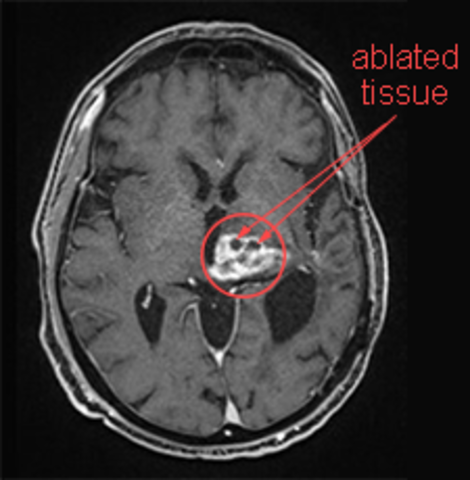

• Brain Ablation Experiments

Brain Ablation Experiments

Brain ablation involves disabling, destroying or removing selected brain tissue followed by an assessment of subsequence changes in behaviour. French physiologist Pierre Flourens is credited for introducing brain ablation experiments. He worked mainly on pigeons and rabbits, developing techniques of damaging or removing small areas of brain tissue to observe the effects on behaviour.